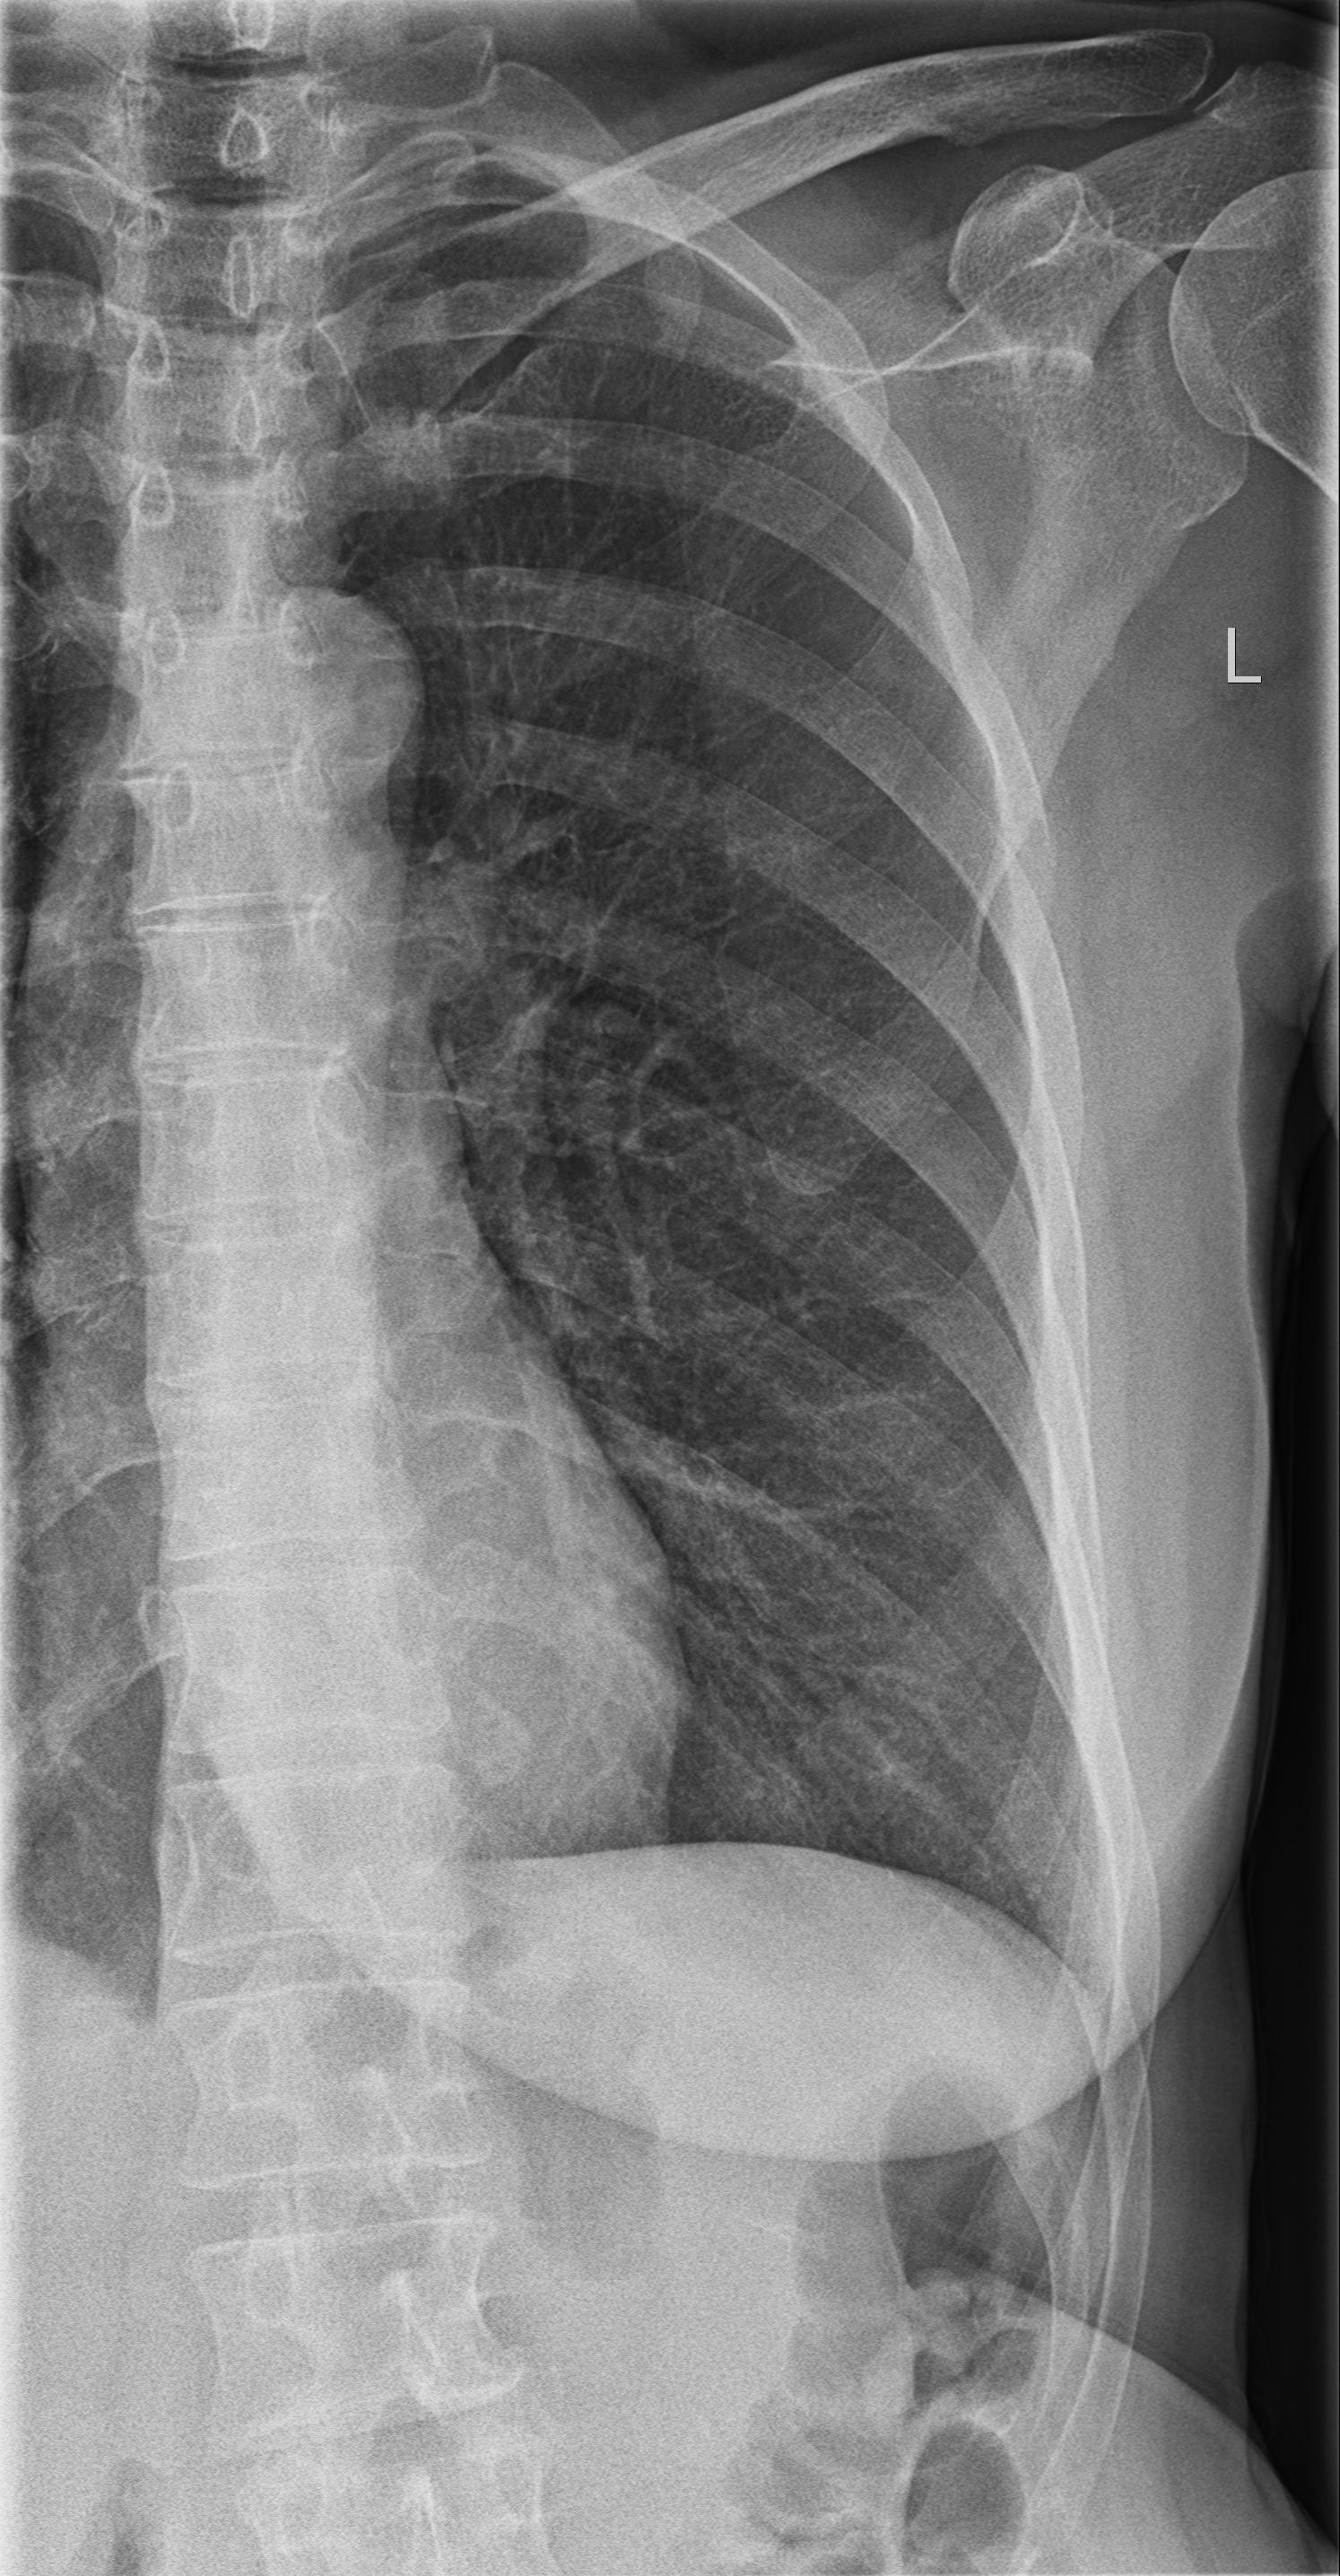

Thorax p.a. & Thorax seitlich

- Thorax ap + Songraphie (Pleura, Perikard, Abdomen) Großzügige CT-Indikation!

- Beurteilungskriterien:

| - pathologische Aufhellungen? |

| - pathologische Verschattungen? |

| - Rippenfrakturen? (vgl. unten) |

| - Mediastinalverlagerung? |

| - Mediastinalverbreiterung? |

| - Zwerchfellkontur und –position? |

| - Tubusverlagerung? |

| - Herz? |

| - Fremdkörper? |